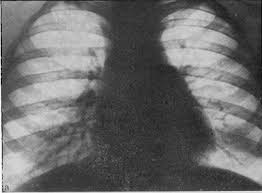

Повод для дифференциального диагноза с констриктивным перикардитом может дата так называемый синдром верхней полой вены

У таких больных часто наблюдаются одутловатость и цианоз лица, значительное набухание шейных вен.

Для дифференциального диагноза имеет значение определение венозного давления в локтевой вене, которое может достигать 400 мм вод. ст., и в системе нижней полой вены (бедренная вена), где оно остается нормальным.